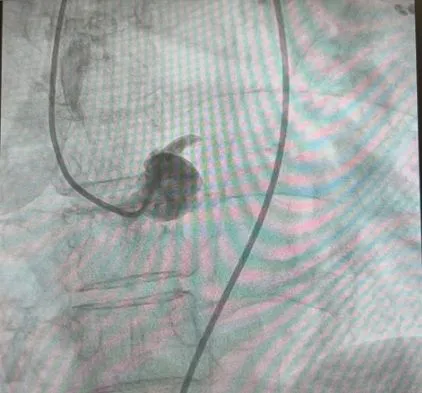

李元真术前造影,显示左主干中段完全闭塞